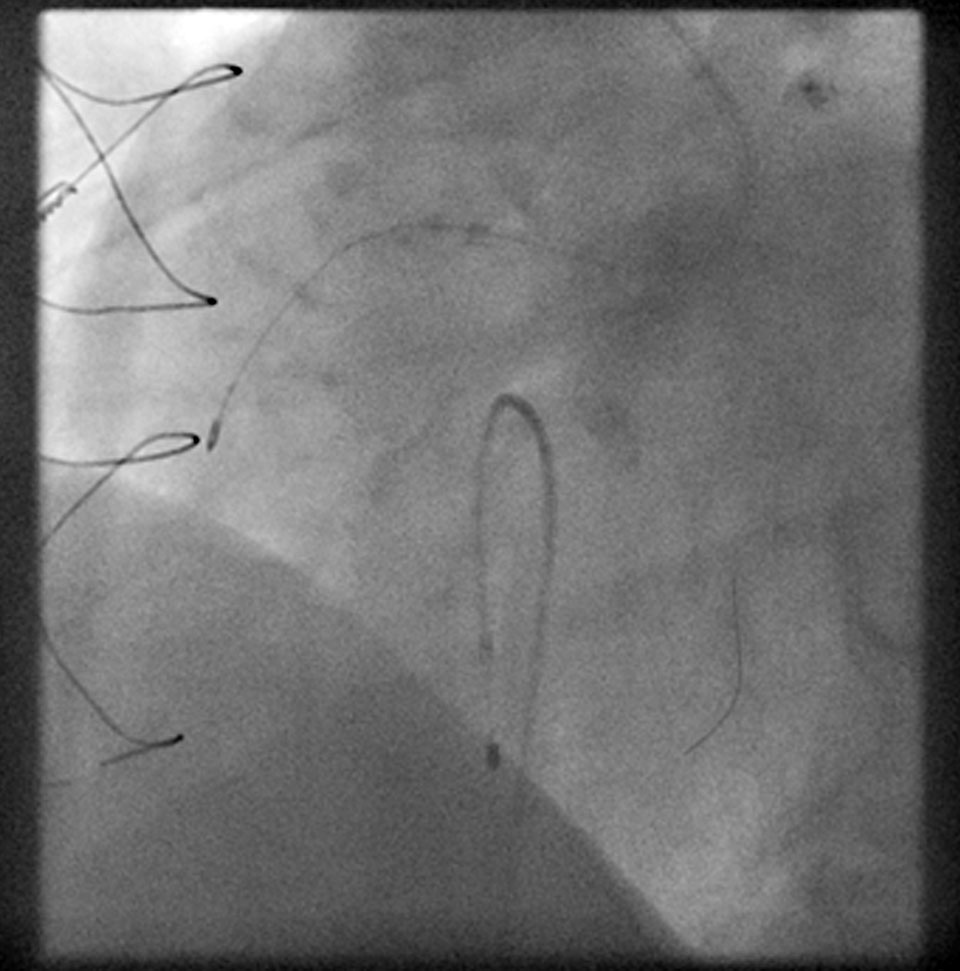

Eine FFR-Messung lässt die Schwere der Durchblutungsstörung in den Koronararterien erkennen und ermöglicht es dem Arzt, genau die Läsionen zu identifizieren, die den Blutfluss behindern, somit für die Ischämie (d. h. Minderdurchblutung des Herzens) verantwortlich sind und durch Stenting behandelt werden können. Die Messungen in den Koronararterien helfen dem Arzt bei der Entscheidung, wann und in welchen Koronararterien eine Therapie sinnvoll ist. Bei dieser Methode wird ein hauchdünner Draht – z.B. der PressureWire™ Agile Tip – durch einen Führungskatheter in die Herzkranzgefäße vorgeschoben. Am vorderen Ende ist ein mikroelektronischer Chip in Form eines Sensors integriert. Dieser Sensor, der in etwa den Durchmesser eines Schmetterlingfühlers hat, misst den Blutdruck an jeder Stelle in den Arterien.

Der Druck wird jeweils vor und hinter der Engstelle gemessen. Anschließend wird ein Zustand maximaler Durchblutung hergestellt und der Druck hinter der Engstelle noch einmal gemessen.

Die Messung der iFR („instantaneous wave-free ratio“) ist eine leicht anwendbare Methode zur invasiven Evaluation von Koronarstenosen ohne Vasodilatanzien und eine Alternative zur FFR-Messung. Im Unterschied zur FFR ist keine Medikamentengabe bei der Messung erforderlich, ansonsten ist der Untersuchungs-Ablauf ähnlich wie bei der FFR. Über einen Herzkatheter wird ein Druckdraht in das Gefäß hinter die zu messende Verengung vorgebracht und anschließend die Messung durchgeführt. Der Grenzwert beträgt <=0,89. Nach bisherigen Studien ist sie der bislang genutzten Fraktionelle-Flussreserve-(FFR-)Messung mindestens klinisch ebenbürtig.

Bei IVUS handelt es sich um einen intravaskulären Ultraschall. Hierbei wird über einen Führungskatheter und einen Führungsdraht ein dünner Katheter, welcher einen sehr kleinen Ultraschallkopf nahe der Spitze enthält in das Herzkranzgefäß vorgebracht. Dieses Verfahren ermöglicht die direkte Untersuchung von Engstellen der Herzkranzgefäße, auch kleinere Ablagerungen können erkannt werden. Zusätzlich dient es der Beurteilung der korrekten Lage und Entfaltung von Koronarstents (Gefäßstützen) und der Erkennung von Gefäßeinrissen (Dissektionen).